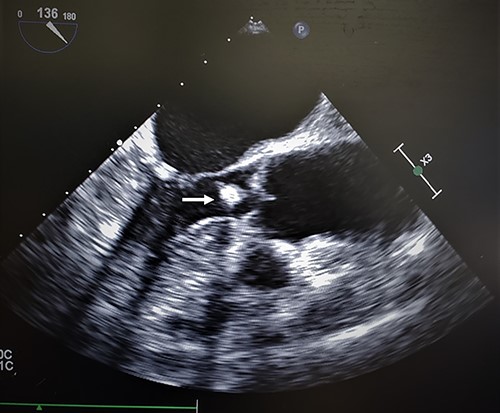

Intraoperative transesophageal echo (TEE) revealed similar findings as to the TTE (Fig. 1). The mass appeared to be pedunculated and appeared to be associated with the noncoronary cusp of the aortic valve. The hyperechoic sphere-like mass moved with each ventricular contraction. The mass moved across the aortic valve into the sinus of Valsalva without evidence of aortic insufficiency.

Transesophageal echocardiogram of cardiac amorphous tumor within the LVOT; intraoperative TEE revealed similar findings as a TTE in the outpatient setting; the hyperechoic sphere-like lesion can be identified within the LVOT in the mid-esophageal bicaval view (white arrow); the mass was mobile and nonobstructive to the LVOT; the attachment site was not visualized clearly.